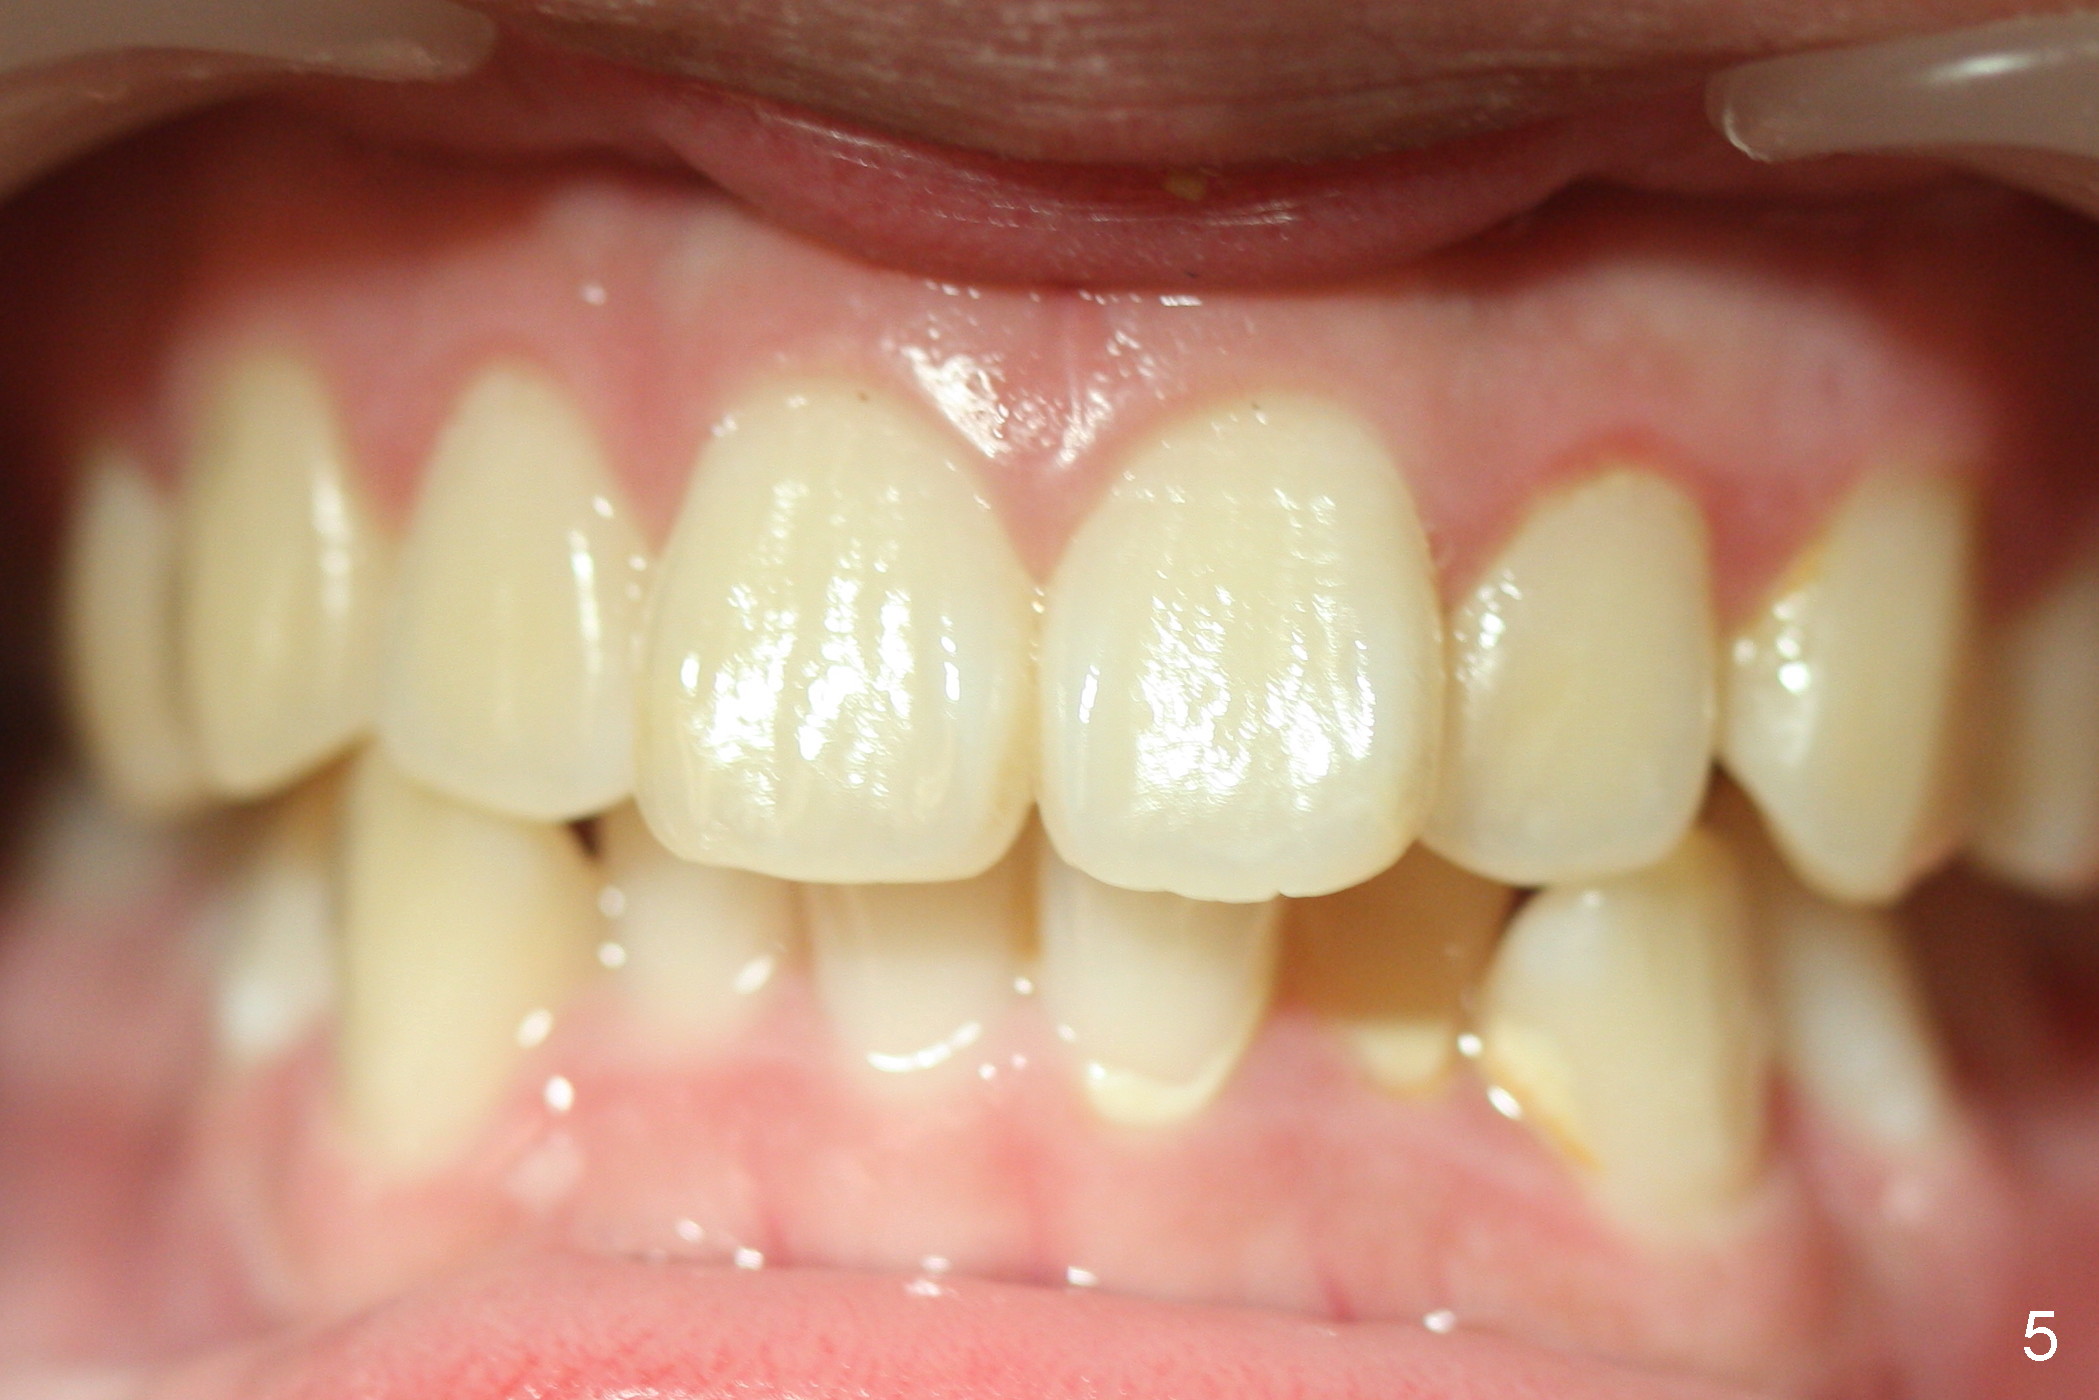

A 15-year-old man wants to improve the facial appearance.

Xin Wei, DDS, PhD, MS 1st edition 02/27/2017, last revision 09/09/2018